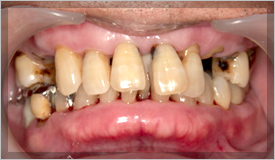

初期ではほとんど症状はありませんが、放置すると進行し、歯が揺れ始め、

硬いものが 噛みにくくなり、最終的には歯の位置が変わってしまったり、

自然に抜けてしまう恐れすらある恐ろしい病気なのです。

歯槽骨が吸収されて、歯が支えられなくなります。

歯がグラグラ動いてしまい、自然に抜けてしまうこともあります。

この状態まで進行してしまいますと、歯の保存は非常に困難となってしまいます。